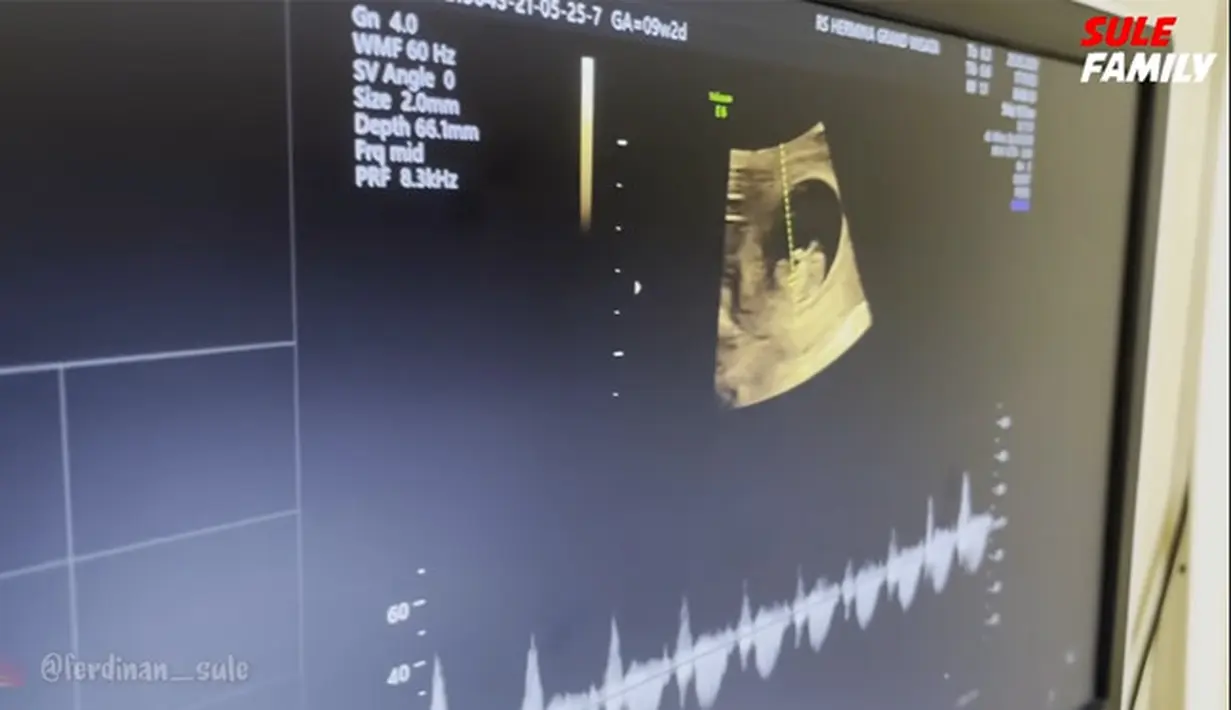

Istri Sule itu mengaku selama tiga hari merasakan pusing. Setelah itu, Natalhie diperiksa dokter melalui USG. Dokter menunjukkan bagian-bagian seperti kepala, badan, tangan yang sesuai dengan usianya dua bulan. Sule dan Nathalie juga mendengarkan denyut jantung janinnya. (Youtube/ SULE FAMILY)

Tampak, perempuan berusia 28 tahun itu terharu hingga mengeluarkan air matanya. Begitu juga dengan Sule yang telah memiliki empat orang anak. Presenter dan komedian itu juga tak terasa air matanya mengalir. (Youtube/ SULE FAMILY)